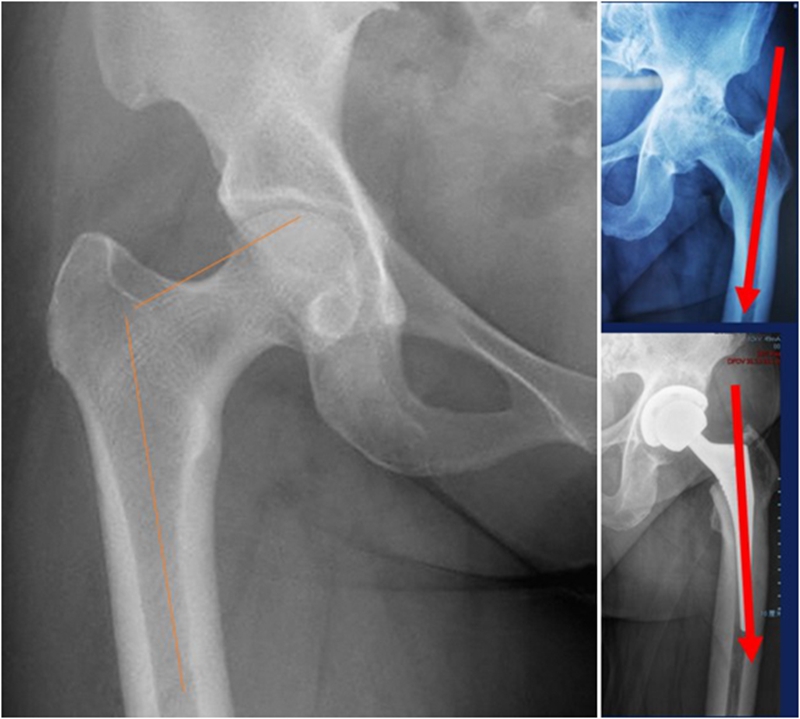

(1)前倾异常增大

先股骨侧操作,根据联合前倾角及各向稳定性决定髋臼前倾,以达最佳稳定。

(3)股骨成角畸形

程度轻,且远离假体安放位置:近端固定短柄假体或小号骨水泥型假体。

严重且靠近假体安放位置:必须行截骨矫正,以获得良好的对线。

纠正性截骨的要求是:

①在畸形最严重的部位纠正对线不良;

②最大限度保留骨质;

③截骨部位牢固固定;

④使用长柄假体跨越截骨端。

股骨截骨的不同方法:

股骨近端截骨重建——截骨方式:横形、斜形、阶梯式及双V形截骨

优点:不改变股骨近端的解剖,保持臀中肌附丽点完整,截骨后能矫正股骨的前倾角,是较为理想的股骨缩短方法。

缺点:①骨折——截骨两端捆钢丝;②截骨端不稳定,术后骨折不愈合——足够长的远端固定型非骨水泥型假体或组配型假体,假体长度足够,避免型号过小,必要时使用骨板加强固定;③失血多、时间长。